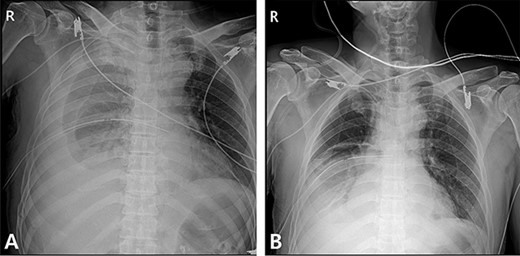

A 59-year-old man was admitted with multiple rib fractures and liver contusion due to a fall injury. He was standing on a chair for working at a farm, and it was knocked over causing him to fall and hit his flank against the corner of the chair. There was continuous pain while resting at the right flank and severe pain with pressure was noted, but no external wounds or bruises were observed. There were right 7th–11th rib fractures, scanty pneumothorax, minimal hemothorax and a 2-cm-sized liver contusion in abdomen and chest computed tomography (CT) scan (Fig. 1A, B). He was hospitalized for pain control and close observation in the general ward, and conservative management was initiated. Also, no significant changes were noted in the following daily follow-up chest radiographs. The patient suddenly complained of right-sided chest and back pain aggravation, cold sweating and fatigue 80 h after the traumatic injury. His mental status was alert, but v/s including systolic blood pressure (SBP) of 100–120 mmHg, heart rate (HR) of 40-60 beats/min and oxygen saturation of 100% during the admission changed to an SBP of 86/60 mmHg, HR of 88 beats/min and oxygen saturation of 97% when the symptoms occurred. Chest radiography was performed after the patient experienced aggravated symptoms, such as right-sided flank pain, cold sweating and fatigue. Compared to the previous scans, signs of increased opacification and peribronchial and parenchymal infiltrations were observed, which were indicative of hemothorax (Fig. 2A, B). We performed enhanced dynamic chest CT to identify any presence of active bleeding. On the chest CT scan, a large amount of hemothorax was identified in the right lung field along with multiple fractures of the right ribs. However, there were no signs of contrast leakage indicative of active bleeding (Fig. 3). Hemoglobin levels decreased from 13.1 g/dl on the day before the symptoms appeared to 11.5 g/dl at the onset of symptoms and to 9.4 g/dl after 2 h. Four packs of RBC transfusion and fluid were administered to the patient, and he was moved to the intensive care unit for close monitoring. And tube thoracostomy was performed, and 1600 ml of fresh blood was drained (Fig. 4A). The following day, 500 ml of blood was drained through the chest tube, but his v/s were stable (Fig. 4B). The amount of bleeding through the chest tube was decreased, but the drained fluid was fresh blood. And we thought that the remaining hematoma was not effectively drained, so the patient’s respiratory discomfort could persist and cause uneffective ventilation. And then we consulted with the Department of Thoracic Surgery, and video-assisted thoracoscopic surgery (VATS) exploratory thoracotomy was performed to identify the bleeding source caused by displaced rib and evacuate the large amount of hematoma. There was a large volume of hematoma within the pleural space and between the right lower lobe, diaphragm and fissure, but no active bleeding point was located. The fractured right 10th rib pierced through the pleural space and was displaced to the thoracic cavity, which was easily reduced. There was no injury surrounding the diaphragm, and although the general lung and chest wall contusions were severe, there were no signs of lung parenchymal lacerations (Fig. 5A–C). Chest tube drainage was serous, and there was no further bleeding. There were no signs of bleeding or any other abnormal findings on chest CT performed at the outpatient clinic, and the patient had no complaints of any symptoms (Fig. 6A, B).

Radiographic findings. (A) After chest tube insertion. (B) 12 h after chest tube insertion.